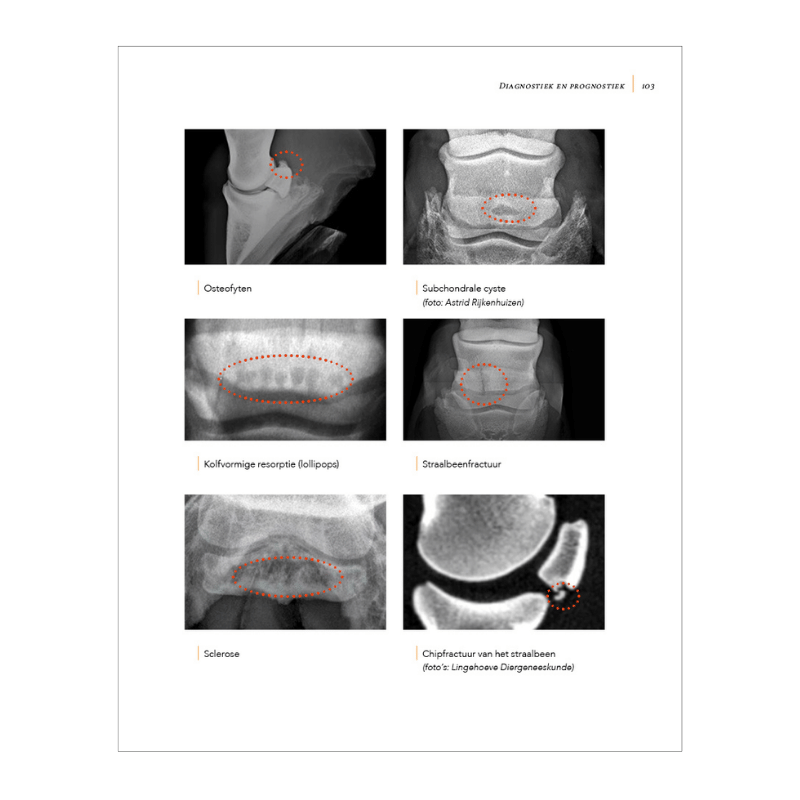

Hoefkatrolontsteking: begrijpen, behandelen, voorkomen is een prachtig boek van 214 pagina’s dat je precies uitlegt wat hoefkatrolontsteking is. Het ontstaan van hoefkatrolontsteking, de ontwikkeling van deze aandoening, de diagnostische technieken en de beschikbare behandelingen worden allemaal uitgebreid besproken. Er is veel aandacht voor het cruciale belang van goede voeding, huisvesting, beweging, training en hoefverzorging. Na het lezen van dit boek weet je hoe je je paard met hoefkatrolontsteking zo goed mogelijk kunt laten behandelen en welke ondersteunende rol jij daarin kunt spelen. Je weet wat je moet doen en laten om te voorkomen dat de situatie verslechtert. Heeft je paard nog geen hoefkatrolontsteking maar wel andere oorzaken van pijn achterin de hoef, dan heb je met dit boek het gereedschap in handen om bijtijds het tij te keren.

Het boek is rijkelijk geïllustreerd met 175 prachtige kleurenfoto’s.

| Beschrijving | 214 prachtige fullcolour pagina’s, 175 afbeeldingen en illustraties |